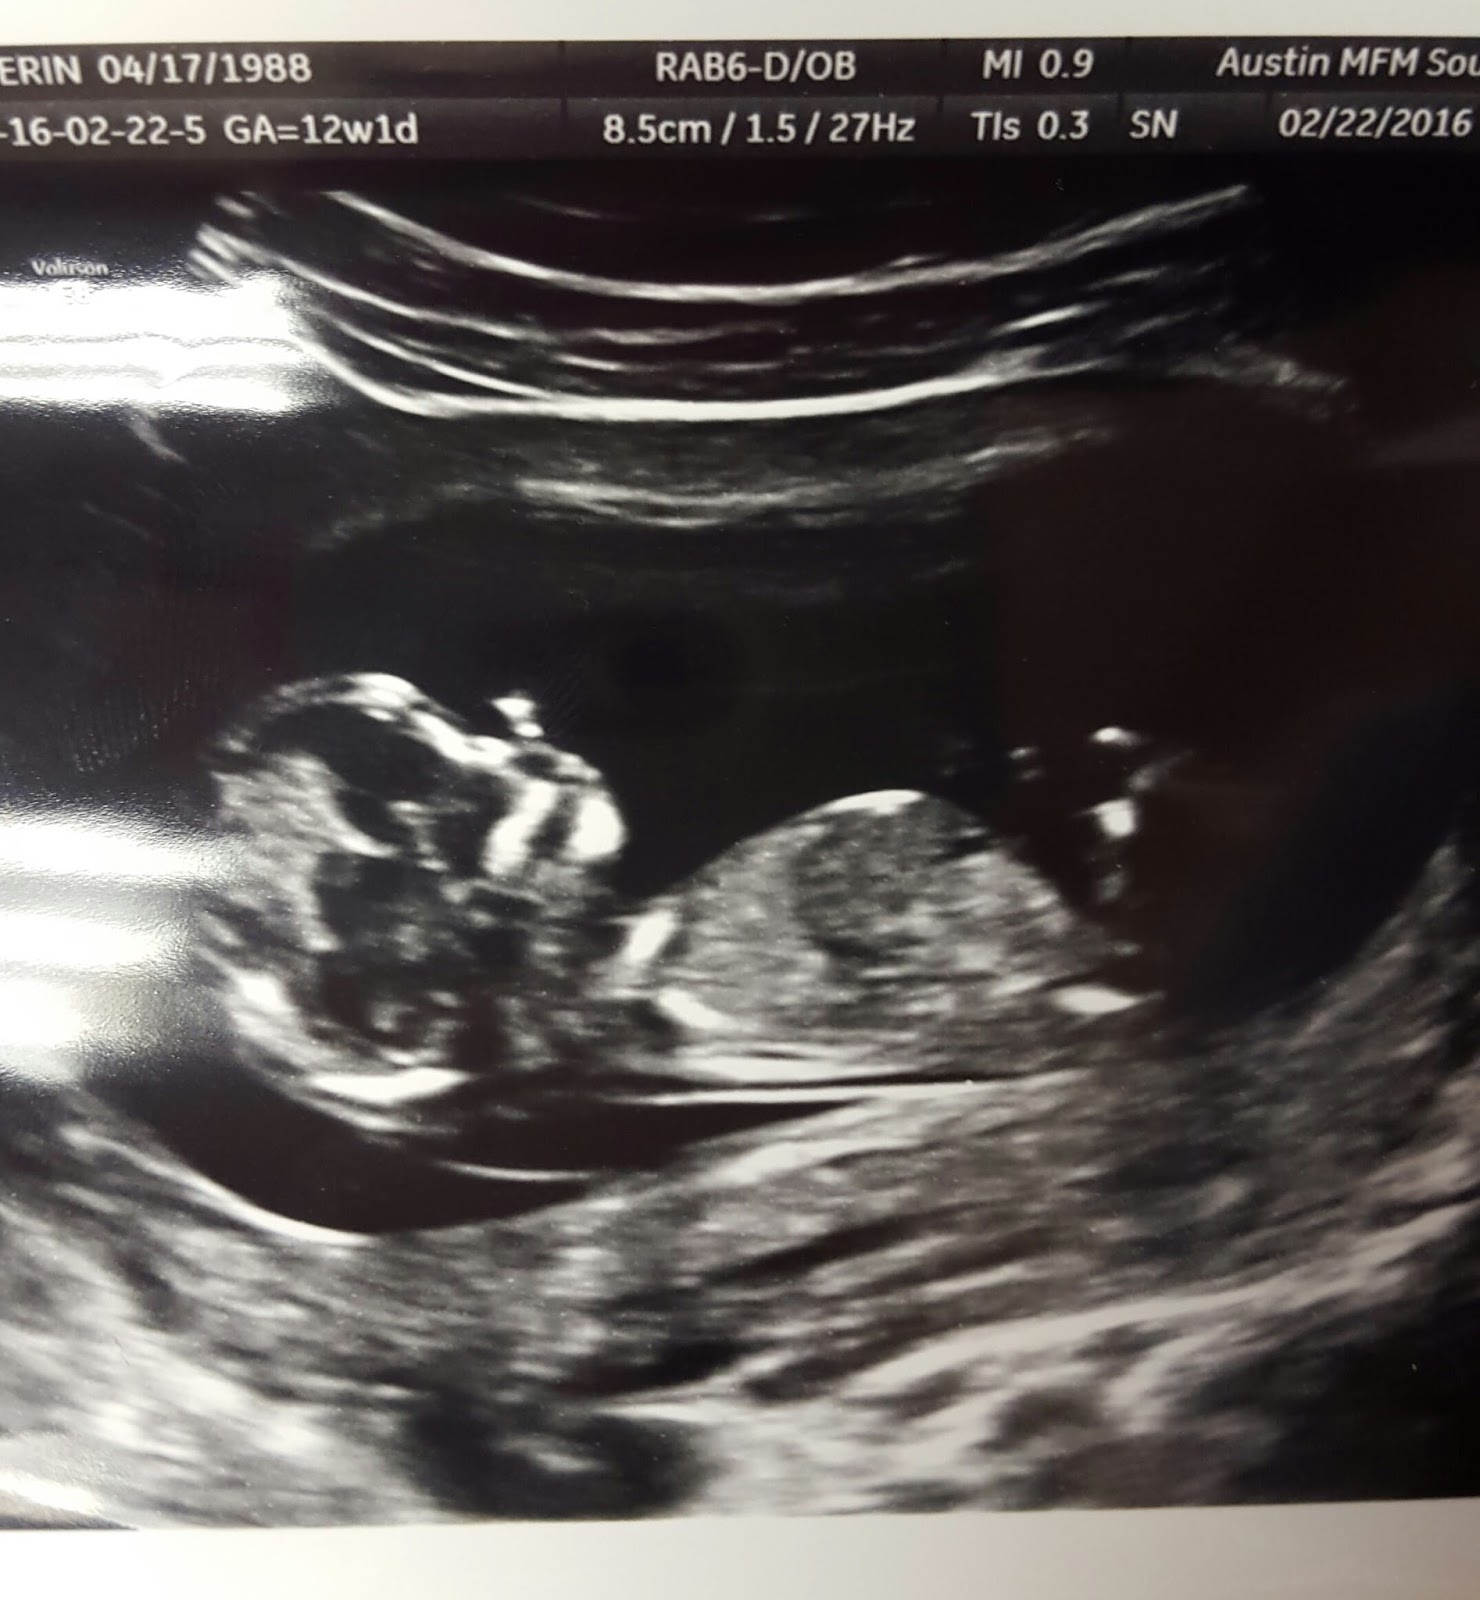

Our appointment yesterday went great! Since baby was ready to be busy and move around a lot, we got to watch on the ultrasound screen for what felt like close to 45 minutes, waiting for baby to get in the right positions for certain measurements! We didn’t mind at all ๐ We got to watch baby flip over, moved arms and hands, kick legs, ans wiggle around!We took video of the screen so I will upload that soon. She even took the 3d/4d (? I’m not really sure what it’s called) pictures! They said there is no way to tell gender from the ultrasound this early, and that’s what we expected her to say.

She says that nothing on the ultrasound gives her any reason to be concerned, and we are waiting on some bloodwork to come back that will give some more verification. And….it will tell us the gender!

Here are some pictures from yesterday! Baby is laid back and hanging out in one. ๐ And thank you for the continued prayers!